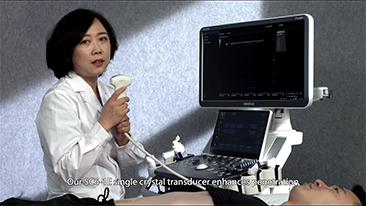

??? ?? ??? ?? ???? ? ??? ?? ??? ?? ??? ??? ??? ???. ???? ??? UWN+ ?? ?? ??? ?? MI??? ??? ??? ?? ?? ??? ?? ?? ?? ???, ?? ?? ?? ???? ??? ? ????.

?? ?? ?? ??? ?? ?? ?? ???? ?? ???? OBG ?????? ?????. ?? ??, ?????(CNS) ??? ?? ?? ??? ?? ? ?????. ???? ?? ??? ?? ??? ??? ??? ?? MSP? 2D ????? ?? ???? ?????. ??? ?? ?? ? ??? ??? ???? ?? ???? ? ????.